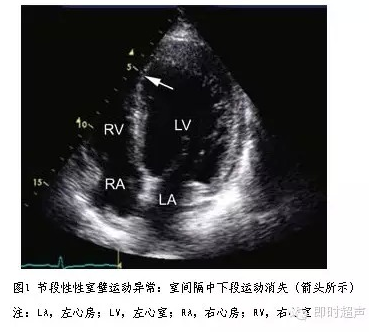

临床常用的有三种:m型,二维和多普勒超声心动图.